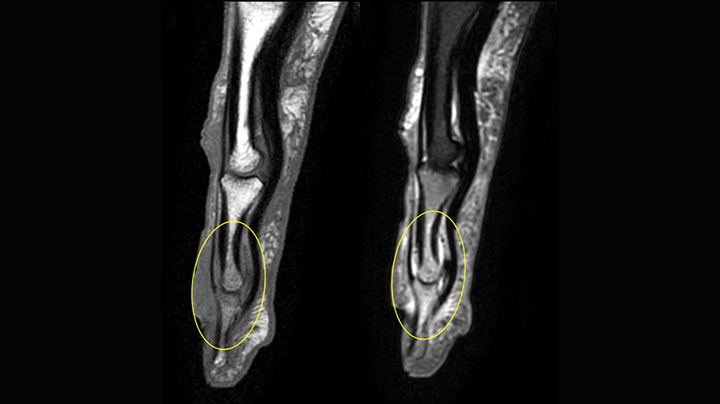

mDIXON TSE of ankle

MRI examination on Prodiva 1.5T of a 72-year-old female with a malignant melanoma in the ankle. mDIXON TSE provides excellent fat

suppression, without the distortion that is often seen at such extremities.

mDIXON TSE of ankle melanoma